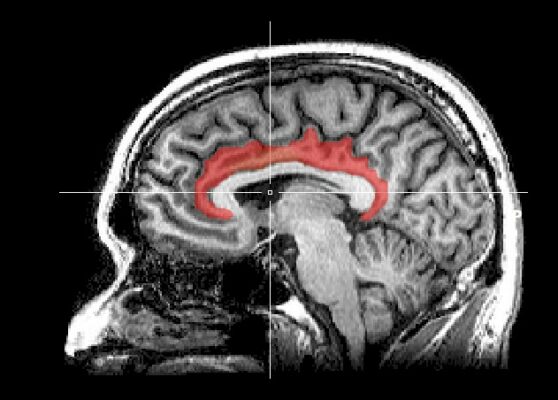

Movement teaches the same lesson from the outside in. Dopamine, serotonin and norepinephrine all respond to physical practice; the basal ganglia rewires habit patterns through repetition; the hippocampus consolidates new motor learning. A 2023 Nature study by Vargas et al. found that classic psychedelics promote structural plasticity by binding intracellular 5-HT2A receptors and triggering dendritic growth (Vargas, Nature 2023). Pair that pharmacology with deliberate movement and breath, and the brain has a clear runway to lay down new pathways.